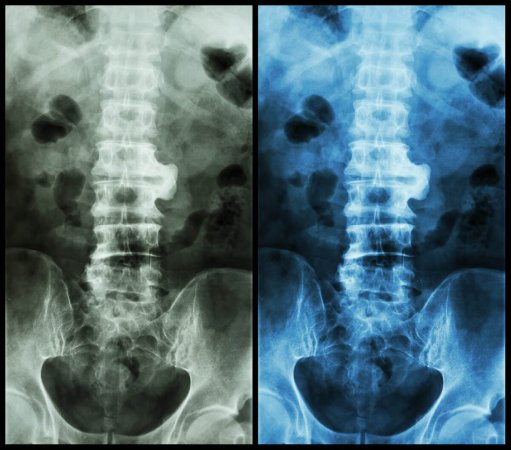

- Görüntüləmə Testləri: X-şüaları (rentgen), MRT (Maqnit Rezonans Tomoqrafiya) və CT taramaları vasitəsilə iltihab və zədələnmələr müəyyən edilir.